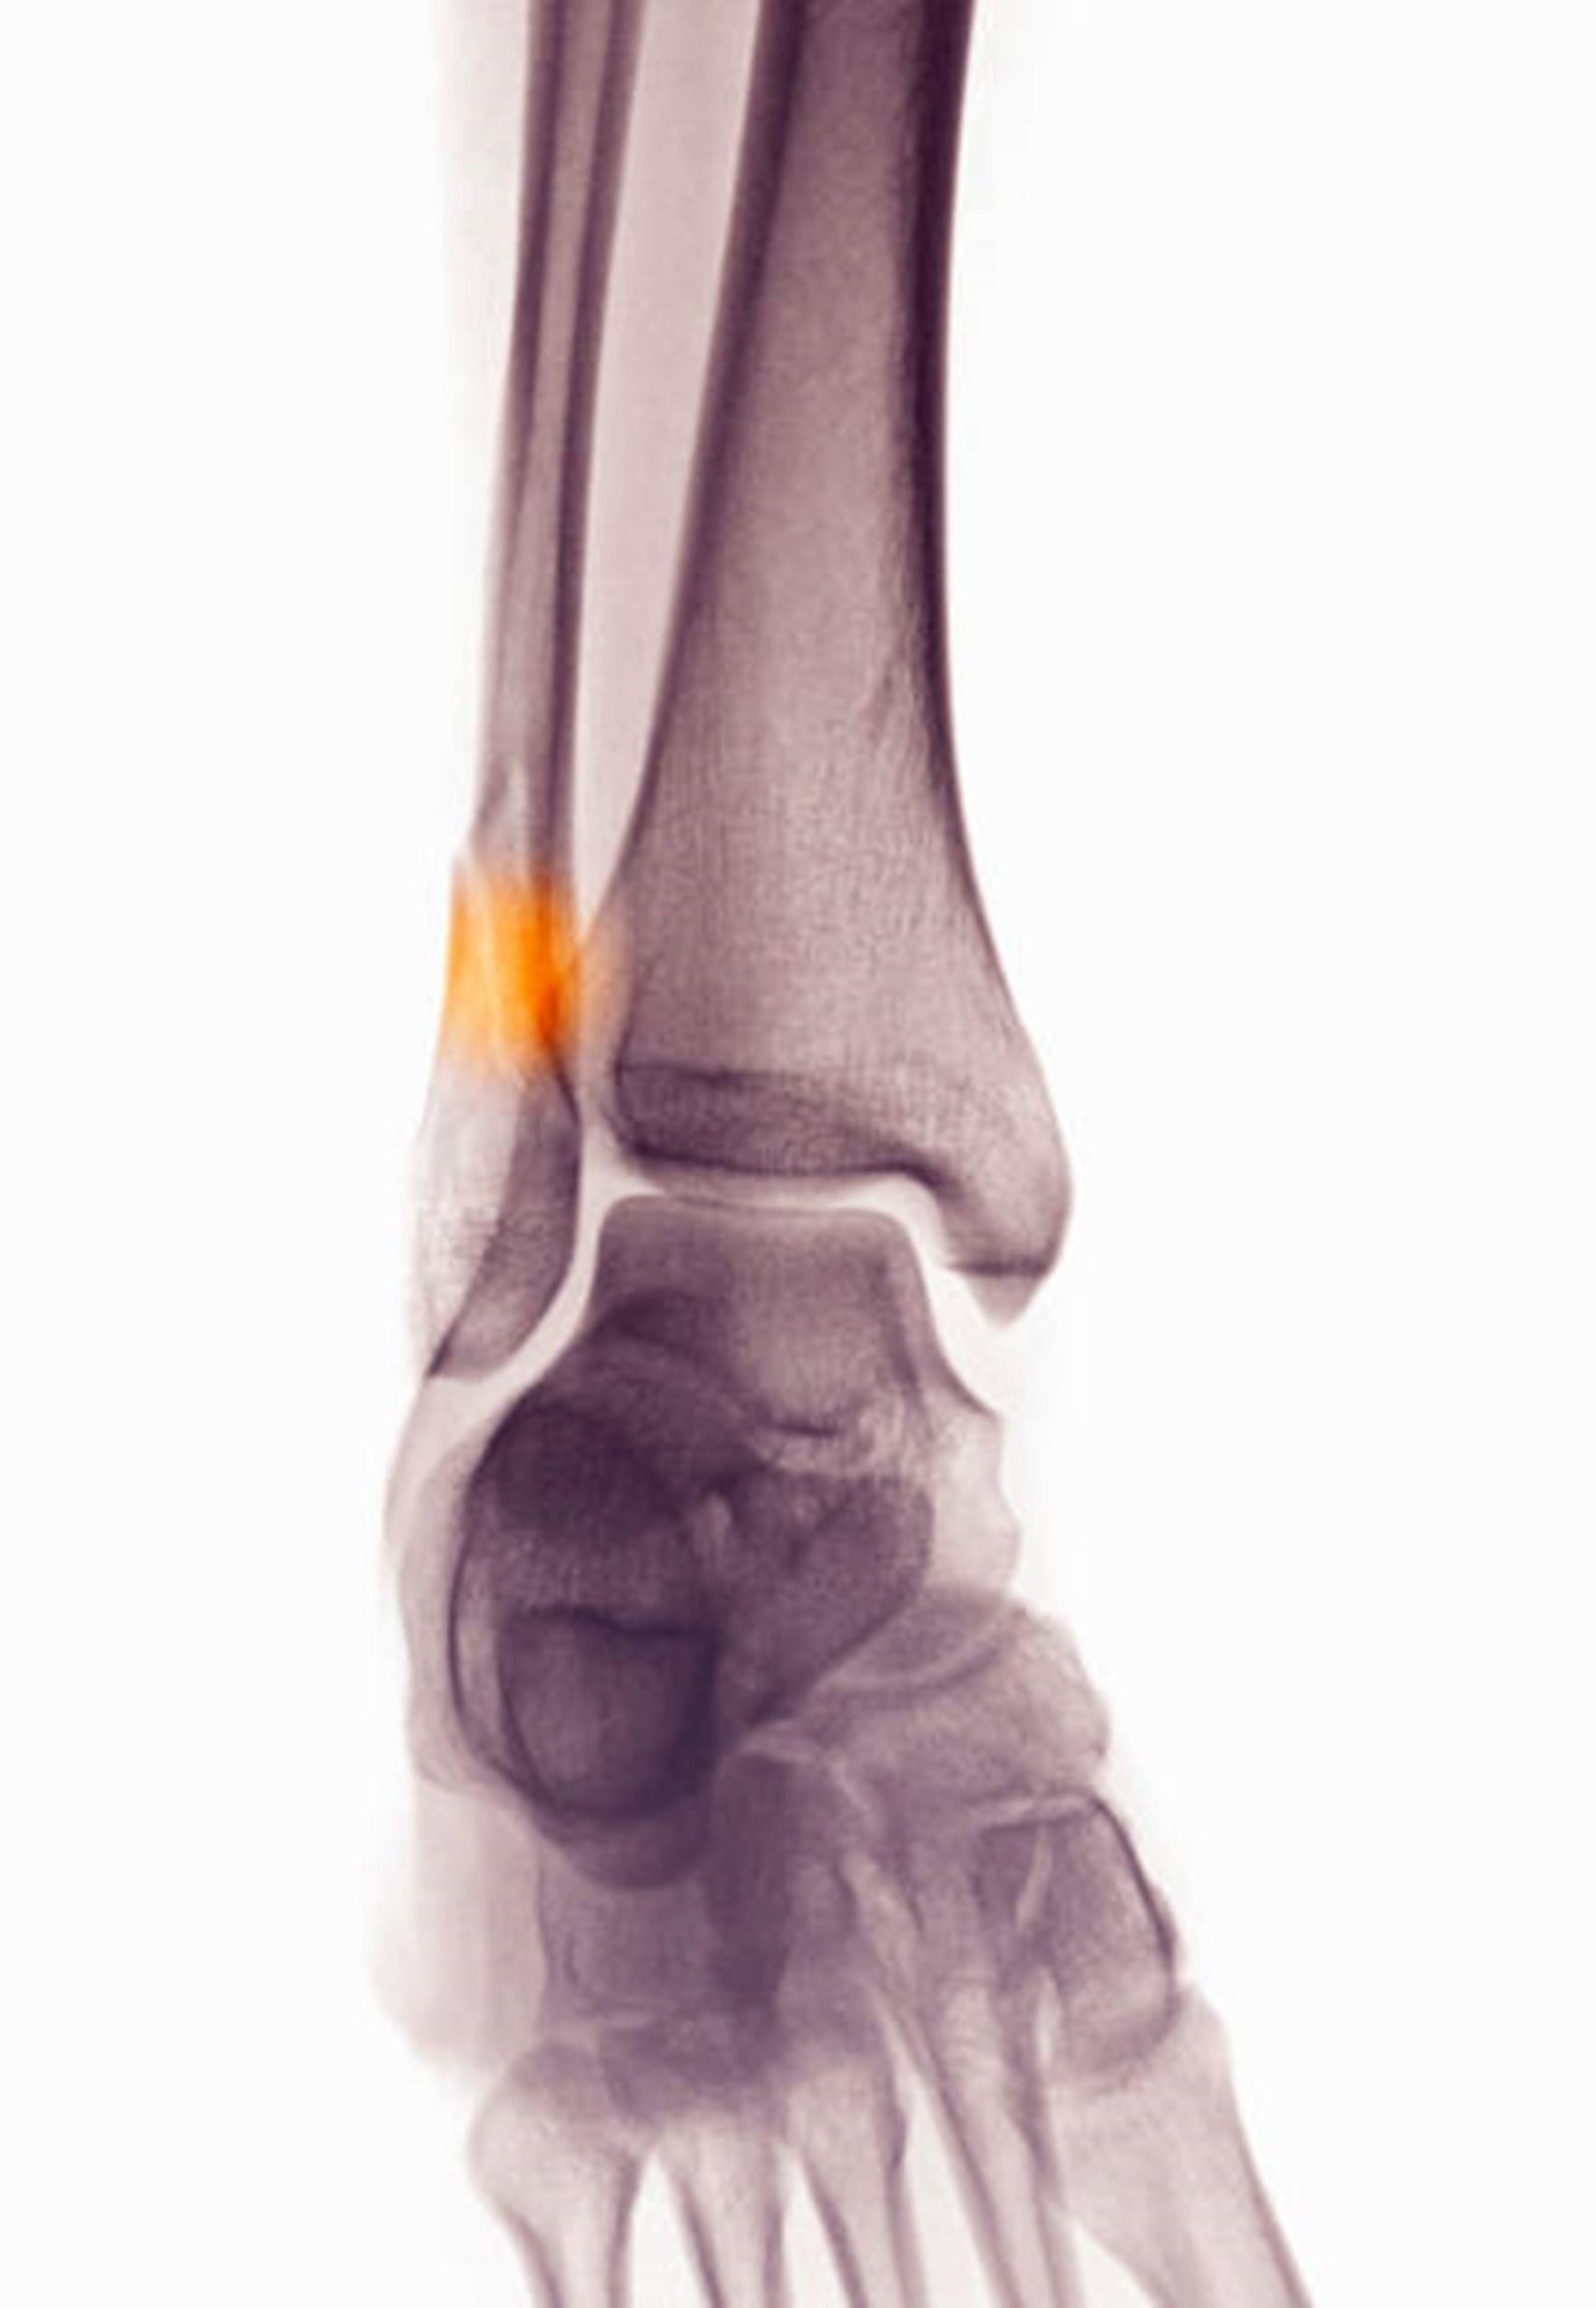

Pictorial representation of arthritis of the ankle

- Arthritis can develop due to osteoarthritis (wear and tear), post-traumatic arthritis (following an injury), or rheumatoid arthritis (an autoimmune condition).

- Symptoms include stiffness, swelling, and pain that worsens with activity. Over time, cartilage wears down, leading to bone-on-bone contact, deformity, and reduced mobility.

- This condition commonly affects middle-aged and older adults or those with a history of ankle injuries.